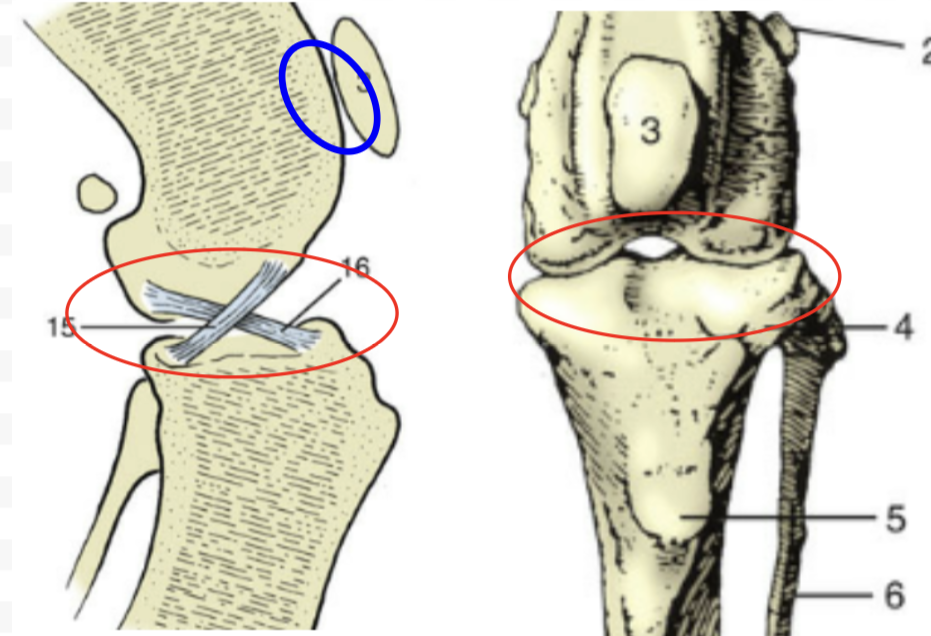

What overall joint?

Stifle

Red circle?

Femorotibular Joint

Blue circle?

Femoropatellar joint